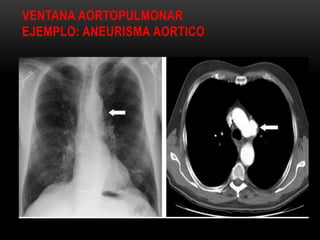

EJEMPLO: ANEURISMA AORTICO

• #21 Figure 11. Aneurysm of the aortic arch. (a) Posteroanterior chest radiograph demonstrates theAP window with a convex border (arrow). (b) CT scan reveals an aneurysm (arrow) arising laterallyfrom the aortic arch, a finding that accounts for the abnormality seen in a.A convex border between the AP window and the lung is considered abnormal. (APRENDER)